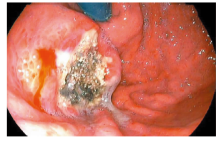

摘要:目的分析和随访内镜下组织黏合剂联合硬化剂注射治疗门静脉高压症胃静脉曲张的疗效及预后。方法研究纳入2006年至2015年期间84例上消化道出血,胃镜检查显示胃静脉曲张,行内镜下组织黏合剂联合硬化剂注射治疗的病人,比较治疗前后出血频率,随访胃静脉曲张消除率及疾病转归。结果84例病人内镜治疗共111例次,平均治疗(1.32±0.68)次/例。内镜治疗前出血(0.72±0.54)次/月,治疗后出血(0.30±0.82)次/月,两者比较差异有统计学意义(P<0.01)。内镜治疗后6个月内胃静脉曲张根除(基本消失)率为75.0%,治疗6个月后为70.8%。术后随访(14.82±19.30)个月内未发生再出血,术后无异位栓塞与感染并发症发生。结论内镜下组织黏合剂联合硬化剂注射治疗有效降低胃静脉曲张出血频率,改善曲张静脉状态,是预防胃静脉曲张再出血的重要方法之一,可在临床应用推广。

Abstract:ObjectiveTo analyze the therapeutic effect of endoscopic injection of tissue adhesive combined with hardener for the portal hypertensive patients with gastric varicose and prognosis.MethodsA total of 84 patients with upper gastrointestinal hemorrhage and gastric varices diagnosed by gastroscopy during 2006 to 2015, who were performed endoscopic injection with tissue adhesive with hardener, were included in this study. The rate of gastric hemorrhage was compared before and after endoscopic treatment. The rate of gastric varices elimination and the prognosis were analyzed.ResultsThere were 111 times of endoscopic treatment for 84 cases with an average of(1.32±0.68) times per case. Bleeding was (0.72±0.54) times/month before treatment and (0.30±0.82) times/month after treatment respectively with significant difference statistically(P<0.01). The eradication rate of varicose veins with almost disappearance was 75.0% during the period of 6 months post endoscopic treatment and 70.8% after 6 months of endoscopic treatment. No re-bleeding was found without any complications, ectopic embolization and infection after follow-up of (14.82±19.30) months.ConclusionsEndosco-pic injection of tissue adhesive and hardener for gastric varices would reduce the rate of bleeding of gastric varicose and the varicose vein, which was an important procedure for prevention of re-bleeding of gastric varicose vein and could be applied clinically.